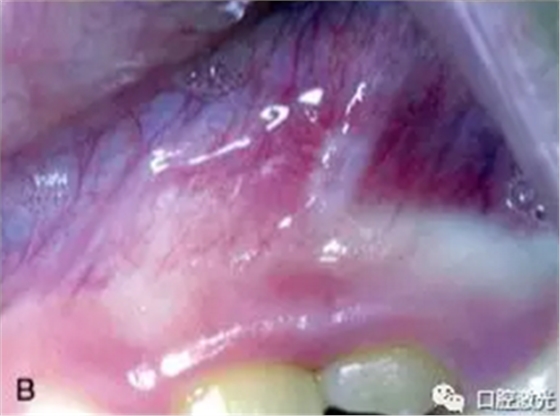

激光口腔潰瘍治療效果A:治療前,B:激光治療4天后

發(fā)生口腔潰瘍時,灼痛是其突出特征,因此顧冠以“阿弗他”名(希臘文aphthous為“灼痛”之意),外觀為單個或者多個大小不一的2-4mm圓形或橢圓形潰瘍,表面覆蓋灰白或黃色假膜,中央凹陷,邊界清楚,周圍黏膜紅而微腫。具有周期性、復(fù)發(fā)性、自限性的特征,年齡不拘,發(fā)病年齡估計在10~20歲之間,女性較多。一年四季均能發(fā)生,能在10天左右自愈,目前病因目前尚未明確。